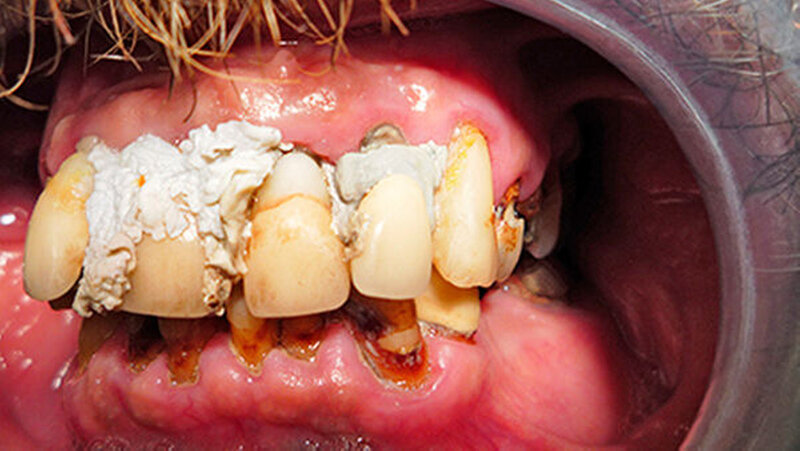

Seine Idee stattdessen: die Zähne selbst zu befestigen. Da er als Handwerker ist er im Umgang mit Baumaterialien versiert ist, sah er sich dieser Herausforderung gewachsen. Er kaufte sich im Baumarkt Fugendichtsilikon und umspritzte damit seine Zähne zur Befestigung. Farblich wählte er "manhattan-grau" und "steingrau" - diese Töne waren billiger als weißes Silikon.

Er achtete auch auf das Biokennzeichen, wie er betonte. Ein halbes Jahr lang war der Patient mit dieser Konstruktion zufrieden. Aber zur Weihnachtszeit gefiel ihm die graue Farbe seiner Silikonbefestigung doch nicht mehr, vielleicht, weil man ihn auch schon auf seine schlechten Zähne angesprochen hatte.